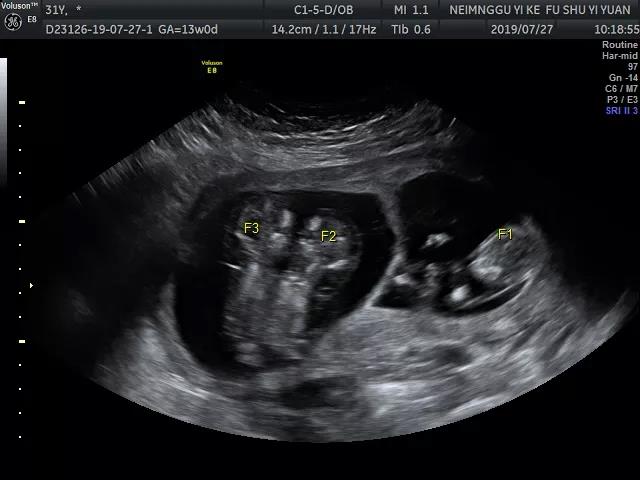

8月15日,超声诊断科福林团队,妇产科孟海霞团队,生殖医学中心陈秀娟团队共同在医院门诊部三楼超声介入室进行超声引导下经腹选择性减胎手术。按穿刺常规要求处理探头及皮肤后,福林将穿刺针快速准确刺入胎儿的心脏,生殖医学中心主任医师刘芳谨慎注入10%氯化钾2.0 ml,被减胎儿出现心律失常,直至胎心停止后再注入0.5 ml氯化钾后迅速拔针。术后5分钟、10分钟用超声监测确认被减胎儿胎心搏动消失,而保留胎儿的心搏正常。

术中照片